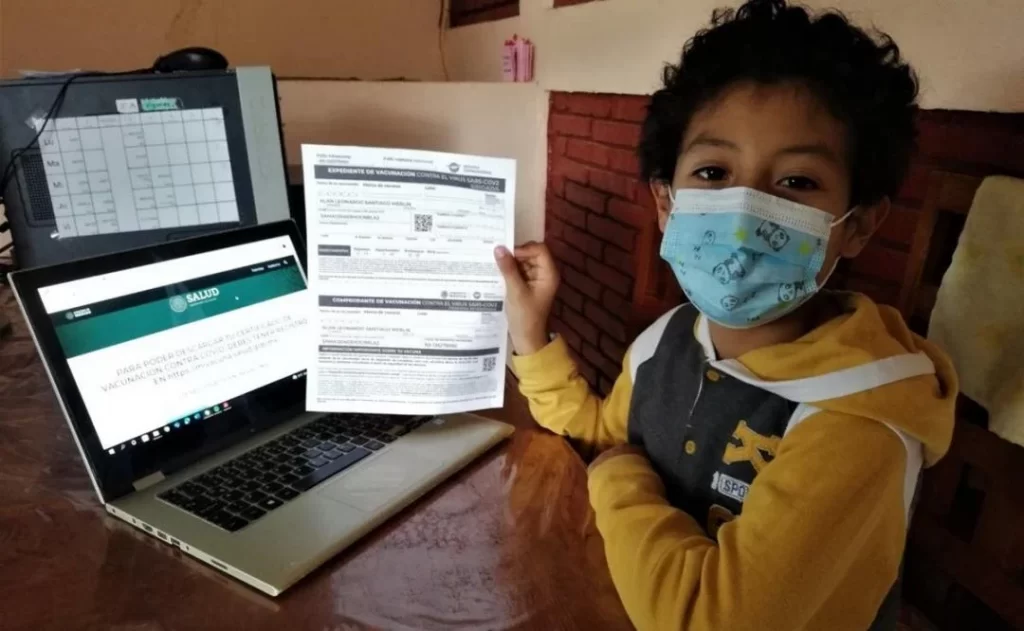

Oaxaca intensifica vacunación contra sarampión, COVID-19 e influenza ante riesgos epidemiológicos

Oaxaca de Juárez, Oaxsca, a 2 de marzo de 2026. – Autoridades de los Servicios de Salud de Oaxaca (SSO) informaron que se reforzó la campaña de vacunación contra sarampión, COVID-19 e influenza en distintas regiones del estado, con el objetivo de prevenir brotes, reducir hospitalizaciones y proteger a grupos vulnerables. La estrategia incluye módulos […]